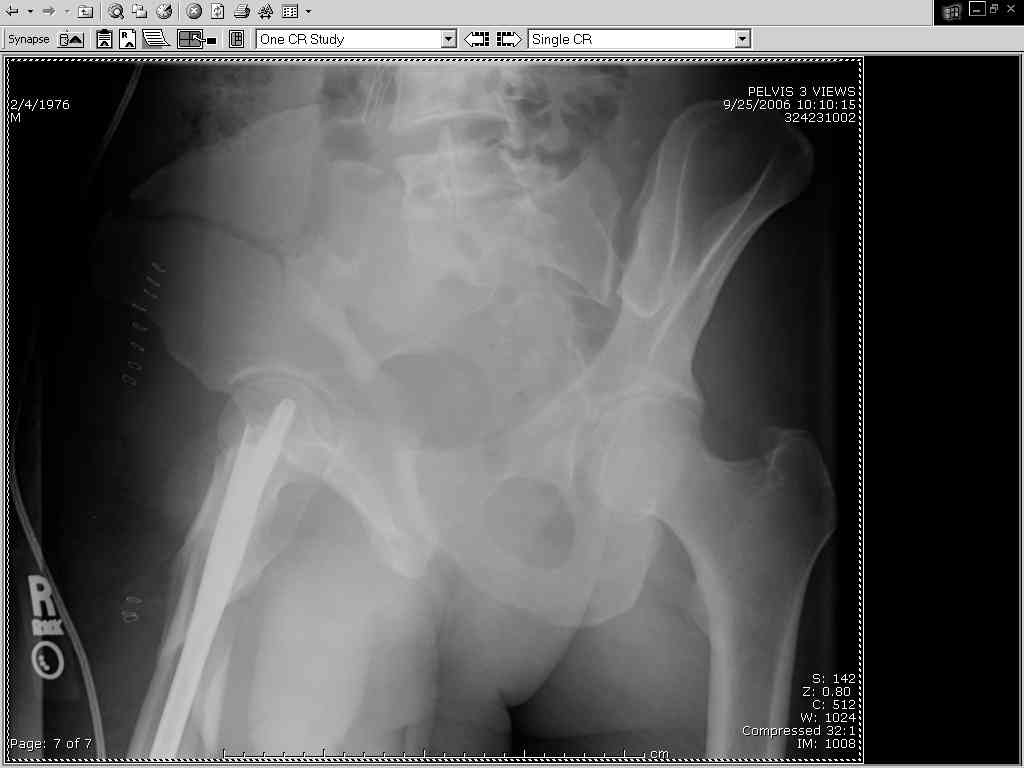

Thanks Adam - I agree it's not a pure APC (is there really such thing as a pure force vector strictly in the x,y or z plane?). I stand corrected. Maybe a hybrid APC (ext rot of L hemipelvis, symphysis disruption, ext rot of R anterior innominate) plus vertical shear as well with 3 or-so cm of cephalad migration of the R ilium. Maybe just "C-type".....

It almost looks to me like an extra-articular both column fx, in addition to the pelvic component. It has the typical triangular fragment and the OO view has a hint of the spur. You may be able to get it all with plates. I would consider fixing the crest first, then a long plate for both symph and iliac portion. SI may close with reduction of symphisis. Looks like the inferior portions are intact. I like your plan as well. You will probably solicit lots of opinion. Good luck. Look forward to post op view.